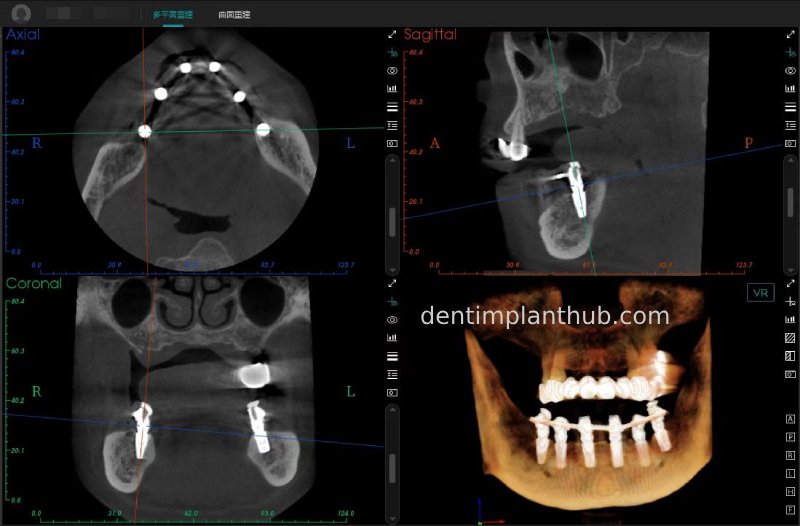

CBCT review results on 13 May '24

46

44

42

32

34

36